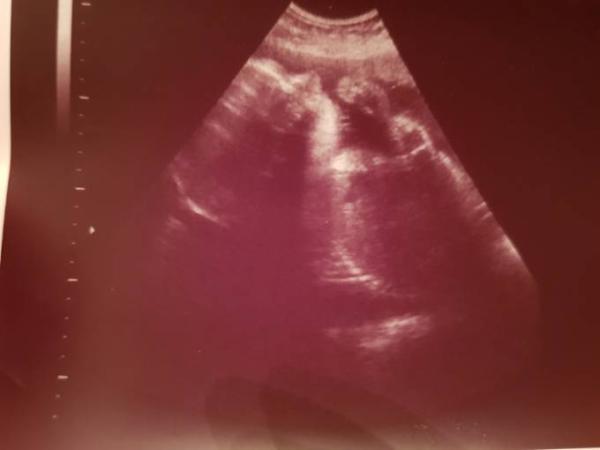

Und alles ist in Ordnung. Mausi ist mit 1300g minimal kleiner und leichter als mein Sohn zu dem Zeitpunkt, aber alles zeitgemäß. Bin heute bei 29+1. Beim CTG und Ultraschall war sie wieder sehr aktiv und hat fleißig geturnt

Bild zu Auch heute 3. Screening gehabt - Forum für Juli - Mamis